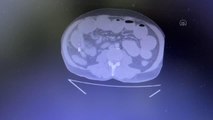

-Zanlının mide ve bağırsak filmleri

- Adana Havalimanında yakalanan, mide ile bağırsağında 49 pakette 775 gram eroin olduğu tespit edilen İranlı kurye, paketleri hastanede tam bir haftada özel ilaçla gözetim altında tek tek çıkardı. Taburcu olan şahıs tutuklandı. Edinilen bilgiye göre olay, 21 Aralık günü Adana Havalimanında meydana geldi. İddiaya göre, Adana Emniyet Müdürlüğü Narkotik Suçlarla Mücadele Şube Müdürlüğünün havalimanında bekleyen sivil ekipleri, Van'dan gelen İran uyruklu Seddigh Raşhıdıtavana (58) isimli şahısın hareketlerinden şüphelendi. Polis, şahsı biraz takip edip daha sonra durdurarak arama yaptı. Ancak herhangi bir suç unsuru bulunmadı. Polisin arama yaptığı sırada şahsın sürekli terlemesinden şüphelenen polis, daha önce bir çok İran uyruklu şahsın uyuşturucu sevkıyatını mide ve bağırsağında yaptığını bilerek bu durumdan şüphelendi. Bunun üzerine şahıs gözaltına alınarak hastaneye götürüldü. "Önce tomografi sonra endoskopi" Polis, şahsın midesinde eroin olabileceğinden şüphelenip hemen hastanenin gastroenteroloji bölümüne götürdü. Burada tomografisi çekilen midede midede sosis büyüklüğünde paketler tespit edildi. Ancak polis, emin olmak için daha sonra şahsa endoskopi işlemi de yaptırdı. Bu sayede ucunda ışıklı küçük bir kamera bulunan ve endoskopi adı verilen bir cihaz yardımıyla şahsın yemek borusu, mide, onikiparmak bağırsağı ve kalın bağırsaklarında 49 paket sosis büyüklüğünde paketler olduğu kesinleşti. "Özel bir ilaç verilerek tuvalet yoluyla bir haftada çıktı" 21 Aralık günü hastaneye getirilen mide ve bağırsağında 49 paket tespit edilen zanlıya özel bir ilaç verildi.